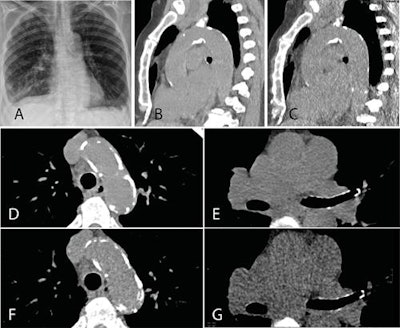

A group from Zürich aimed to determine the value of ultralow-dose chest CT for estimating atherosclerotic burden of the thoracic aorta using tin-filter technology and to compare its diagnostic accuracy with chest x-ray. In the study published online on 3 October in British Journal of Radiology, the team revealed that the technique provides a reliable estimation of burden at x-ray equivalent dose and also showed its diagnostic accuracy was significantly higher than that of x-ray.

Their study included a total of 106 patients, 43 (41%) women and 63 (59%) men, from a prospective single-center study. In the same session, these patients underwent standard-dose chest CT with 110 kV (1.7 ± 0.7 mSv) by clinical indication followed by ultralow-dose CT with 100 kV and spectral shaping by a tin filter (0.13 ± 0.01 mSv) to achieve an equivalent dose to chest. All scans were conducted on a third-generation dual-source CT scanner (Somatom Force, Siemens Healthineers).

Two independent radiologists reviewed the images, rated image quality, and estimated the presence and extent of calcification of the aortic valve, ascending aorta, and aortic arch. X-rays also were included if they were performed within three months from the time the CT study was conducted and if both posteroanterior and lateral views were available (n = 49; 46% of study group). If no chest x-ray was available in this time period (n = 57; 54% of study group), an x-ray mimic was created via a thick multiplanar reformation in both views from the CT dataset of the ultralow-dose scan.

The images of 106 patients, including standard-dose CT, ultralow-dose CT, and chest x-rays, yielded a total of 318 datasets. The researchers found that the sensitivity for detecting thoracic aortic calcification was significantly lower on chest x-ray (52.5%) compared with ultralow-dose CT (p < 0.001).

Furthermore, in terms of the value of ultralow-dose CT for estimation of calcifications, the researchers found a high agreement for calcium quantity estimation between standard-and ultralow-dose CT images with weighted p-values of 0.966, 0.973, and 0.972, in the aortic valve, ascending aorta, and aortic arch, respectively (p ≤ 0.001).

The subjective image quality with regard to the diagnostic value for aortic calcification was rated lower for ultralow-dose CT images with a mean of 3.9 as compared with standard-dose images with a mean of 4.9 (p ≤ 0.001). Only one case (1%) was rated as nondiagnostic for aortic calcium detection on ultralow-dose CT.